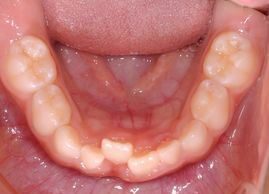

では左の写真のように、乳歯の後ろからおとなの歯が生えてきた場合はどうでしょうか?乳歯よりかなり後方から大きな永久歯が顔を出していますね。

その4にもありましたが、乳歯が抜けて、その場所に大きな永久歯が整列するにはスペースが明らかに不足しています。